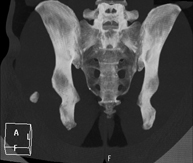

- TC Pelvis Prueba diagnóstica que consiste en obtener imágenes bi y tridimensionales de la pelvis de alta definición anatómica (estructuras óseas, estructuras vasculares, vejiga, útero y ovarios, próstata y vesículas seminales, uréteres, etc.) mediante el empleo de un equipo de TC (Tomografía Computarizada). La mayoría de estudios requieren el empleo de contraste yodado. Prueba diagnóstica que consiste en obtener imágenes bi y tridimensionales de la pelvis de alta definición anatómica (estructuras óseas, estructuras vasculares, vejiga, útero y ovarios, próstata y vesículas seminales, uréteres, etc.) mediante el empleo de un equipo de TC (Tomografía Computarizada). La mayoría de estudios requieren el empleo de contraste yodado.

- TC Abdominopélvico Prueba diagnóstica que consiste en obtener imágenes bi y tridimensionales del abdomen y de la pelvis de alta definición anatómica (estructuras óseas, estructuras vasculares, hígado, páncreas, vesícula biliar, riñones, glándulas suprarrenales, bazo, intestino delgado y grueso, vejiga, útero y ovarios, próstata y vesículas seminales, uréteres, etc.) mediante el empleo de un equipo de TC (Tomografía Computarizada). La mayoría de estudios requieren el empleo de contraste yodado. Prueba diagnóstica que consiste en obtener imágenes bi y tridimensionales del abdomen y de la pelvis de alta definición anatómica (estructuras óseas, estructuras vasculares, hígado, páncreas, vesícula biliar, riñones, glándulas suprarrenales, bazo, intestino delgado y grueso, vejiga, útero y ovarios, próstata y vesículas seminales, uréteres, etc.) mediante el empleo de un equipo de TC (Tomografía Computarizada). La mayoría de estudios requieren el empleo de contraste yodado.